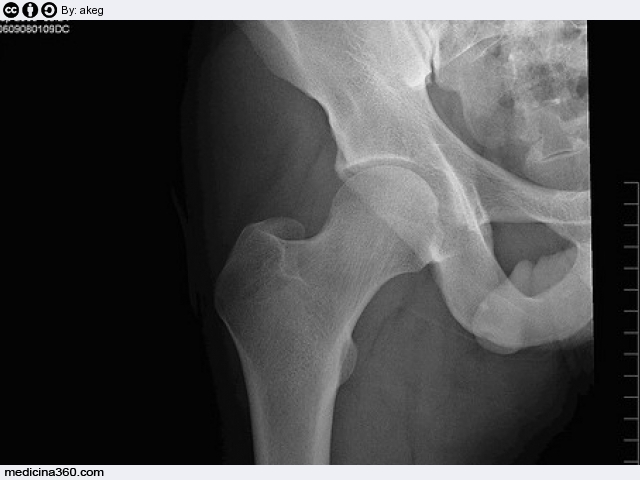

La protesi del femore è utilizzata per trattare la frattura del collo del femore.Vediamo come avviene l'intervento e quando è necessario sostituirla.

La protesi del femore o endoprotesi è utilizzata per trattare, generalmente negli anziani con problemi di osteoporosi, la frattura del collo del femore.

Per via chirurgica viene asportata la parte femorale dell'articolazione dell'anca e sostituita con una protesi di speciale lega metallica. La testa metallica della protesi viene ad articolarsi direttamente nell'acetabolo. La protesi femorale può essere: